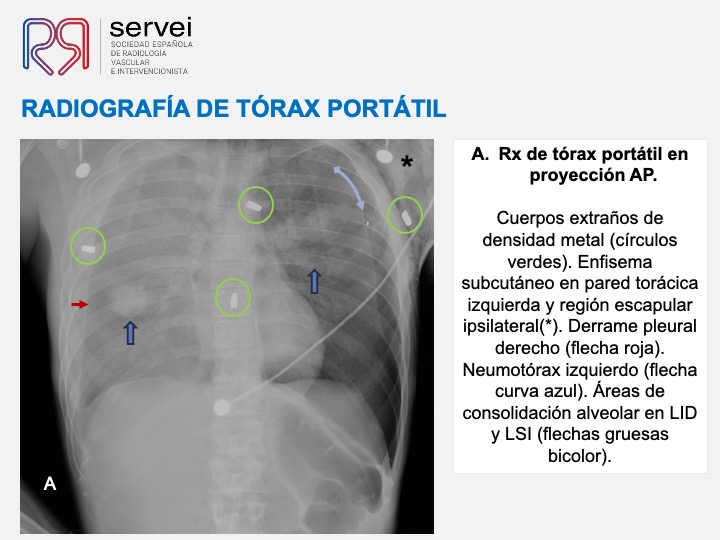

- Pseudoaneurisma pulnonar herida arma fuego 03